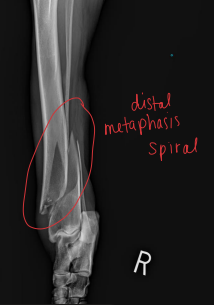

Describe the Fracture

Forces: Tension, compression, bending, torsion, shear

Pattern: Transverse, Oblique, Spiral, Comminuted

Radius & Ulna Fractures

Considerations: No soft tissue envelope, weight-bearing, blood supply poor in small breeds, poor healing, Robert/modified jones bandage

Tx: rigid fixation, often only radius tx

Bone plate & screws (#1)

IM pins contraindicated for radius

IM pins NOT in radius (cats need both)

JUST the radius in fixed(dogs)

External skeletal fixation→ open fractures, 1A ESF

Casting: acceptable if 50% reduction; best for transverse fractures in young dogs

NOT in toy breeds